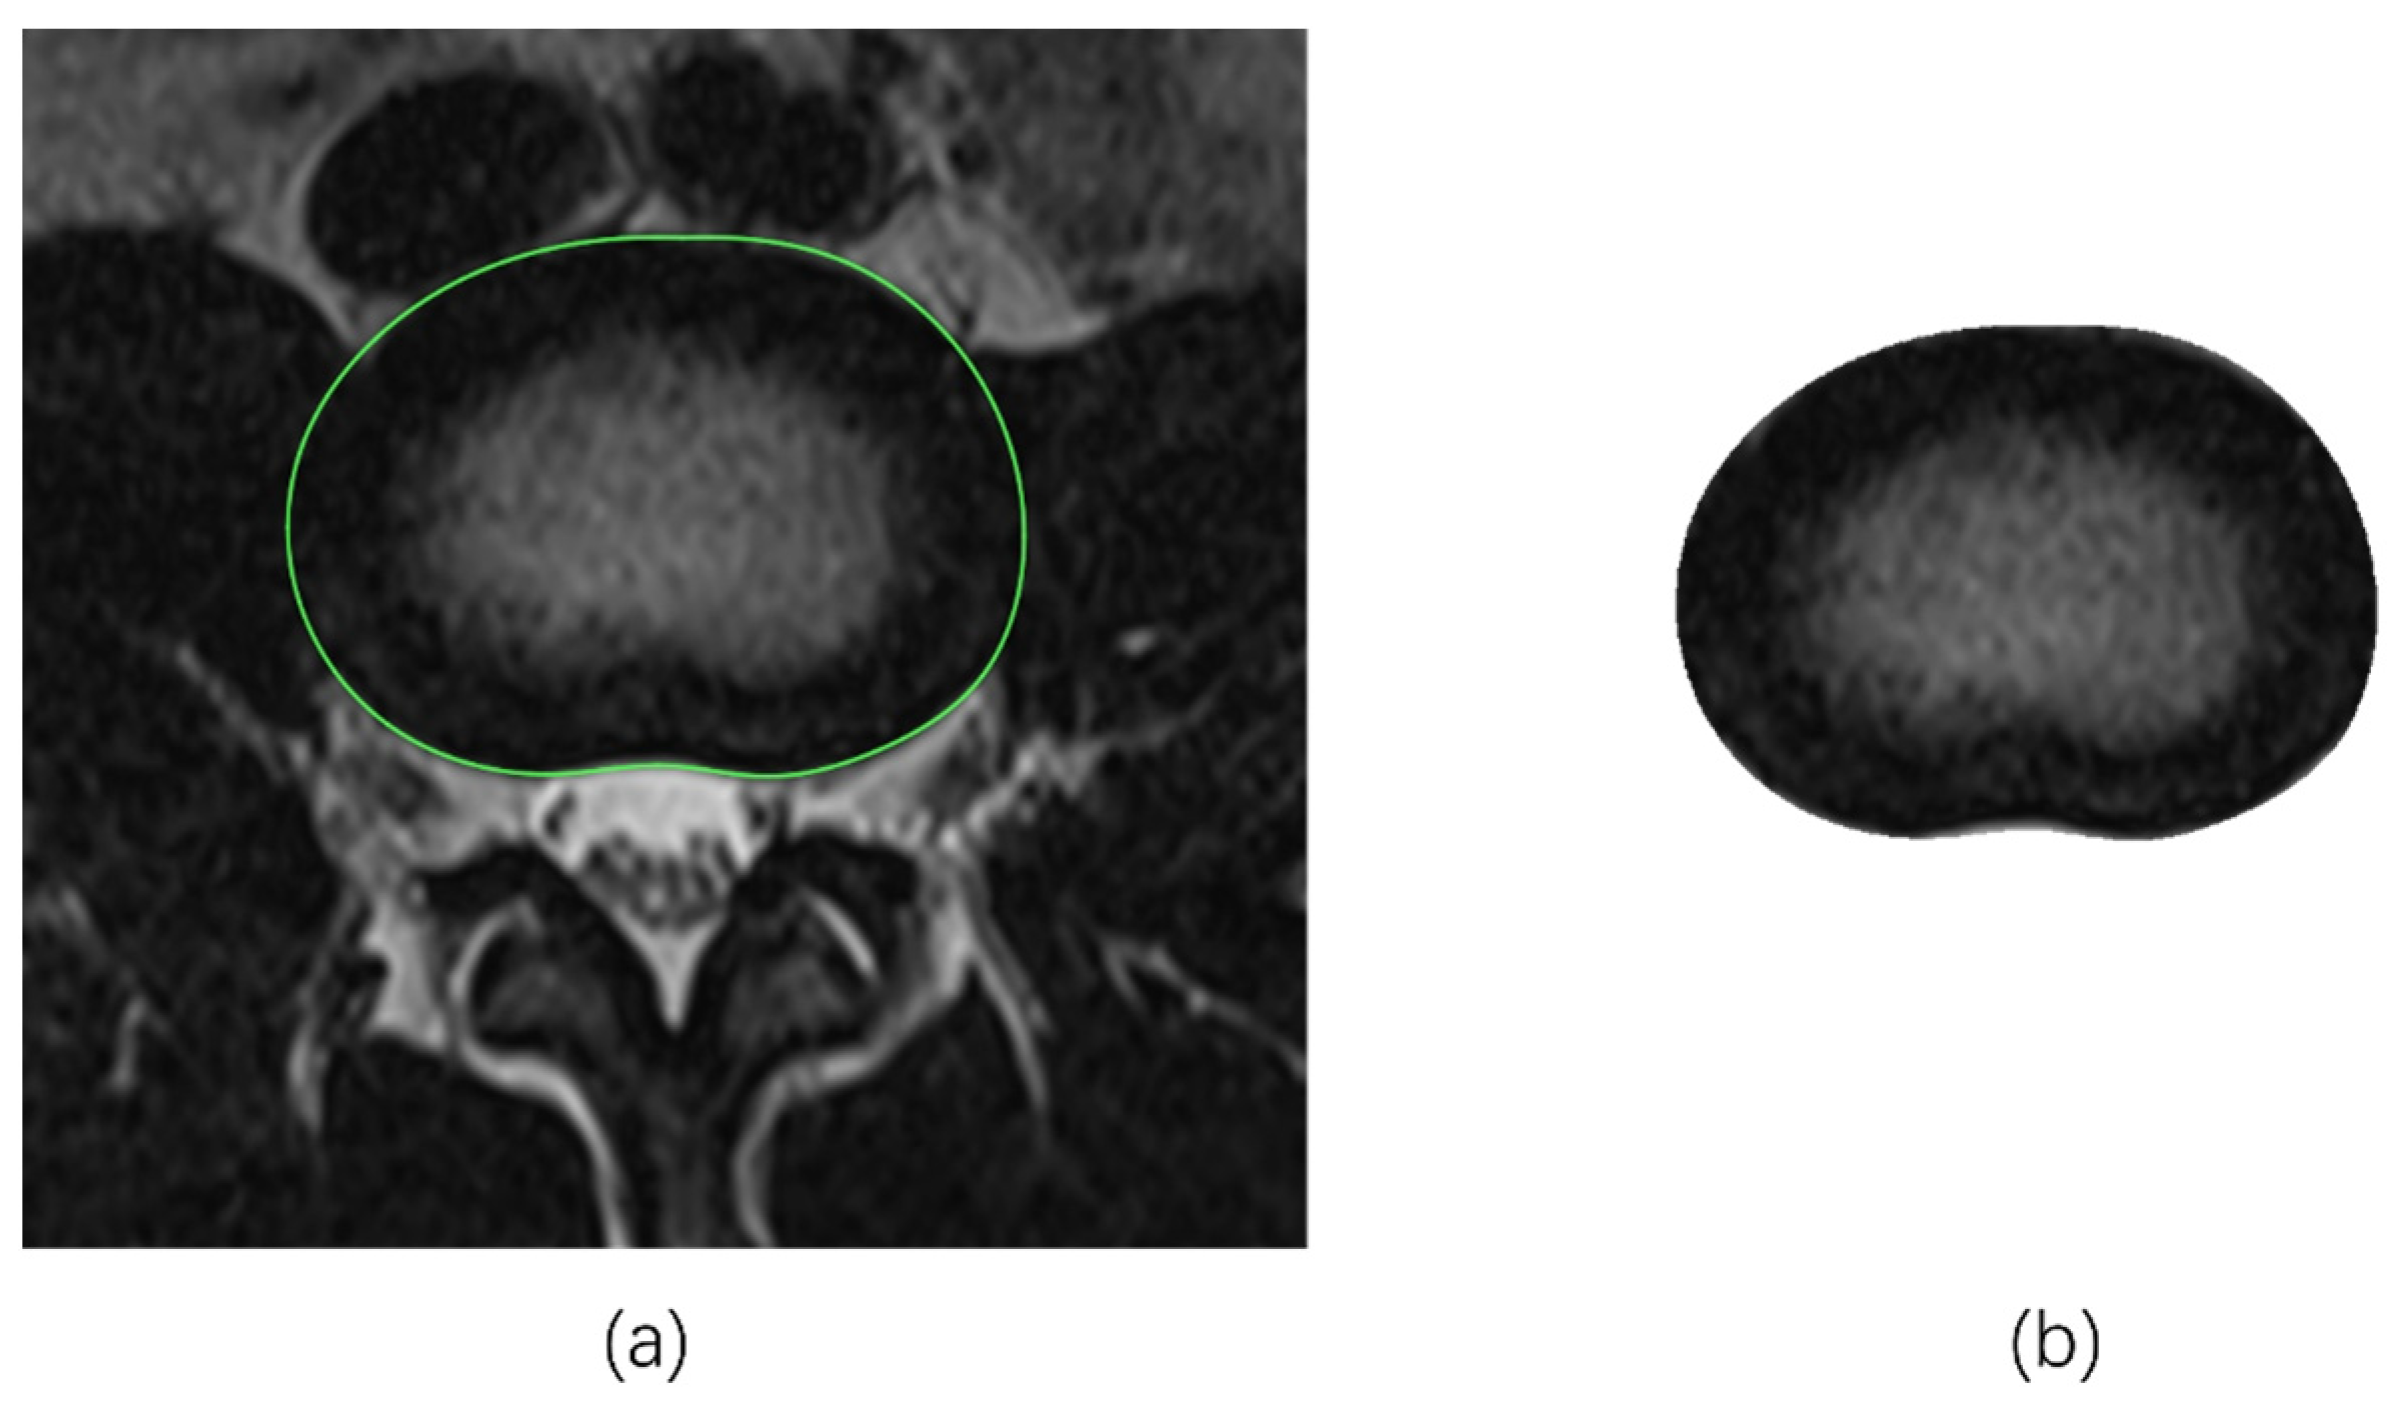

2.2.1. Tracing the IVD Contours

2.2.2. Tracing the NP Contours

- Manual tracing (MT)

2.3. Determination of NP-to-CSA Ratios